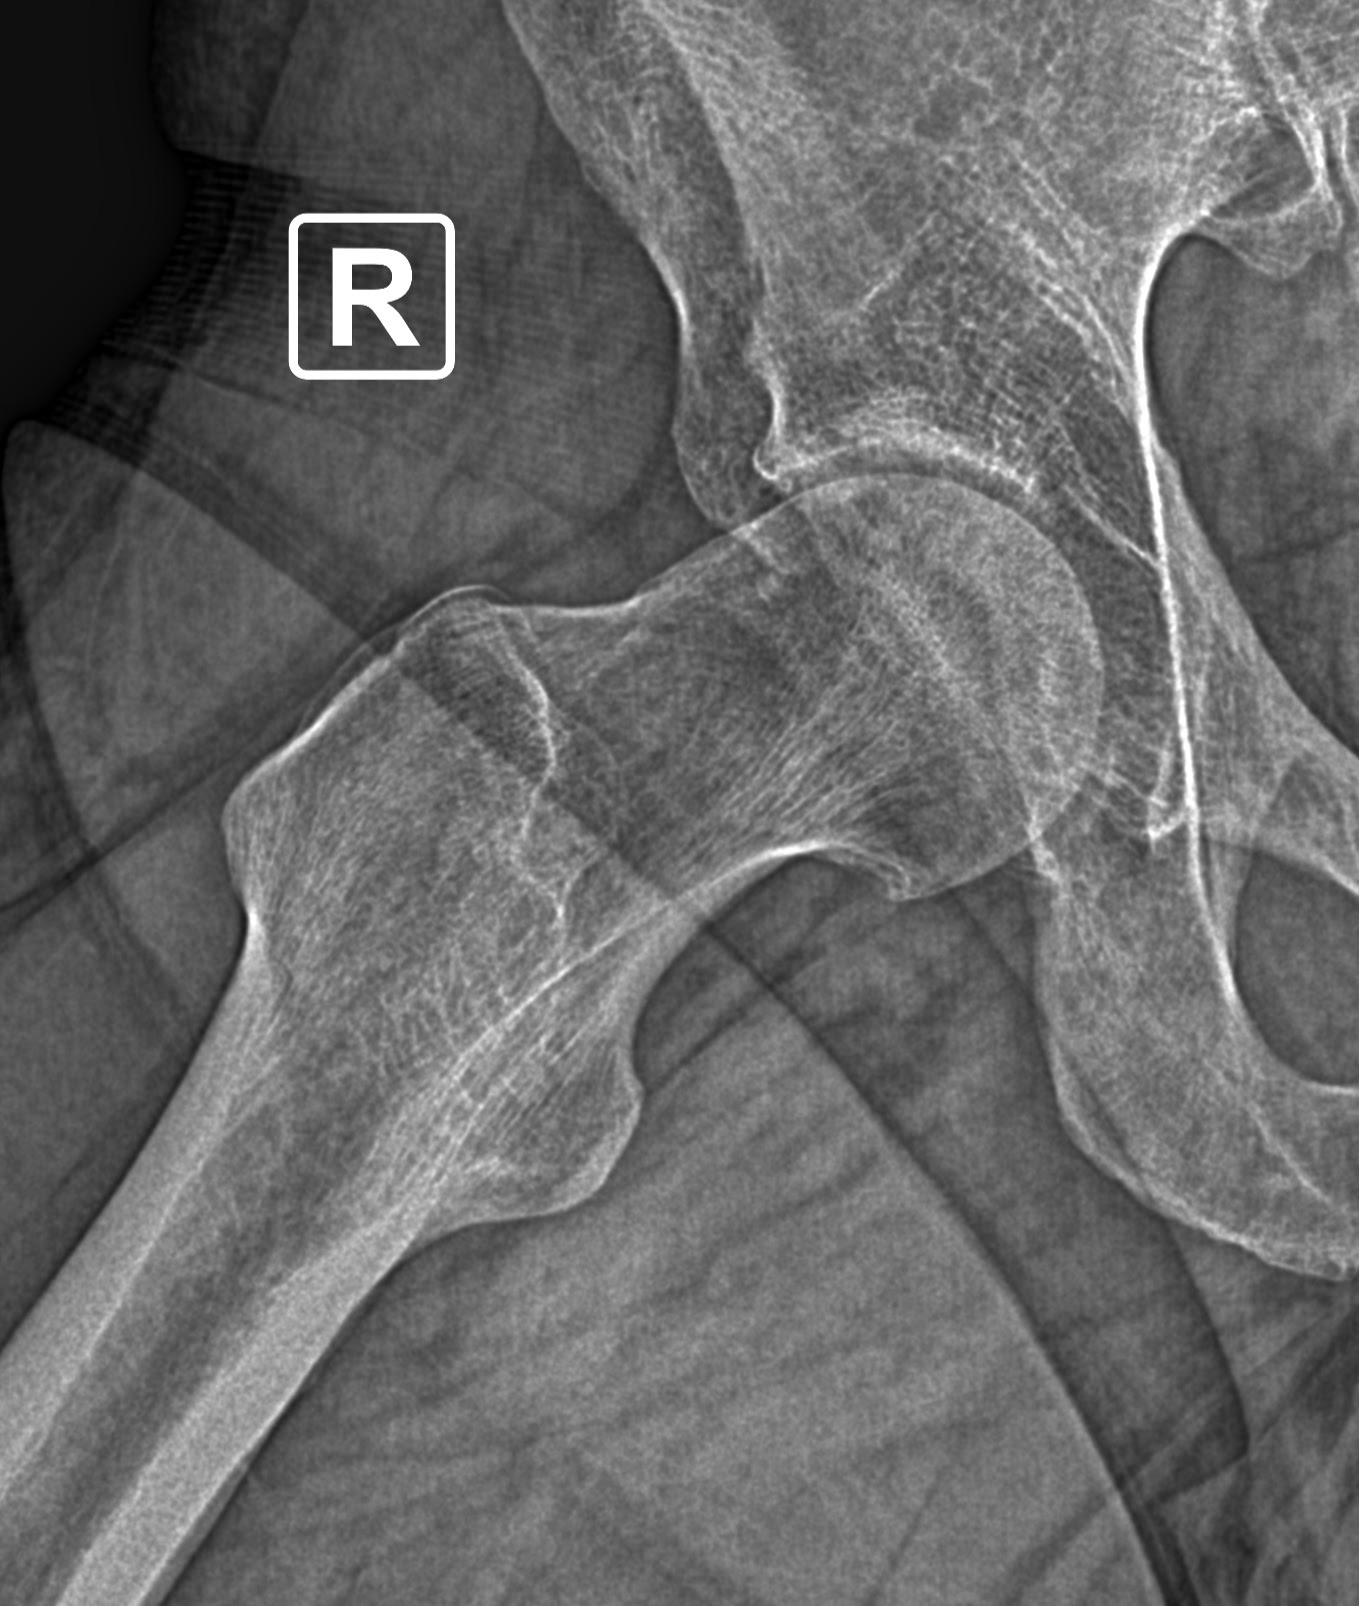

Η γωνία άλφα αποτελεί ένα ποσοτικό χαρακτηριστικό της μηροκοτυλιαίας πρόσκρουσης τύπου cam, σε περιπτώσεις ασθενών με χρόνιο πόνο στο ισχίο. Ωστόσο, τα όρια της γωνίας αυτής αποτελούν ακόμα ένα...